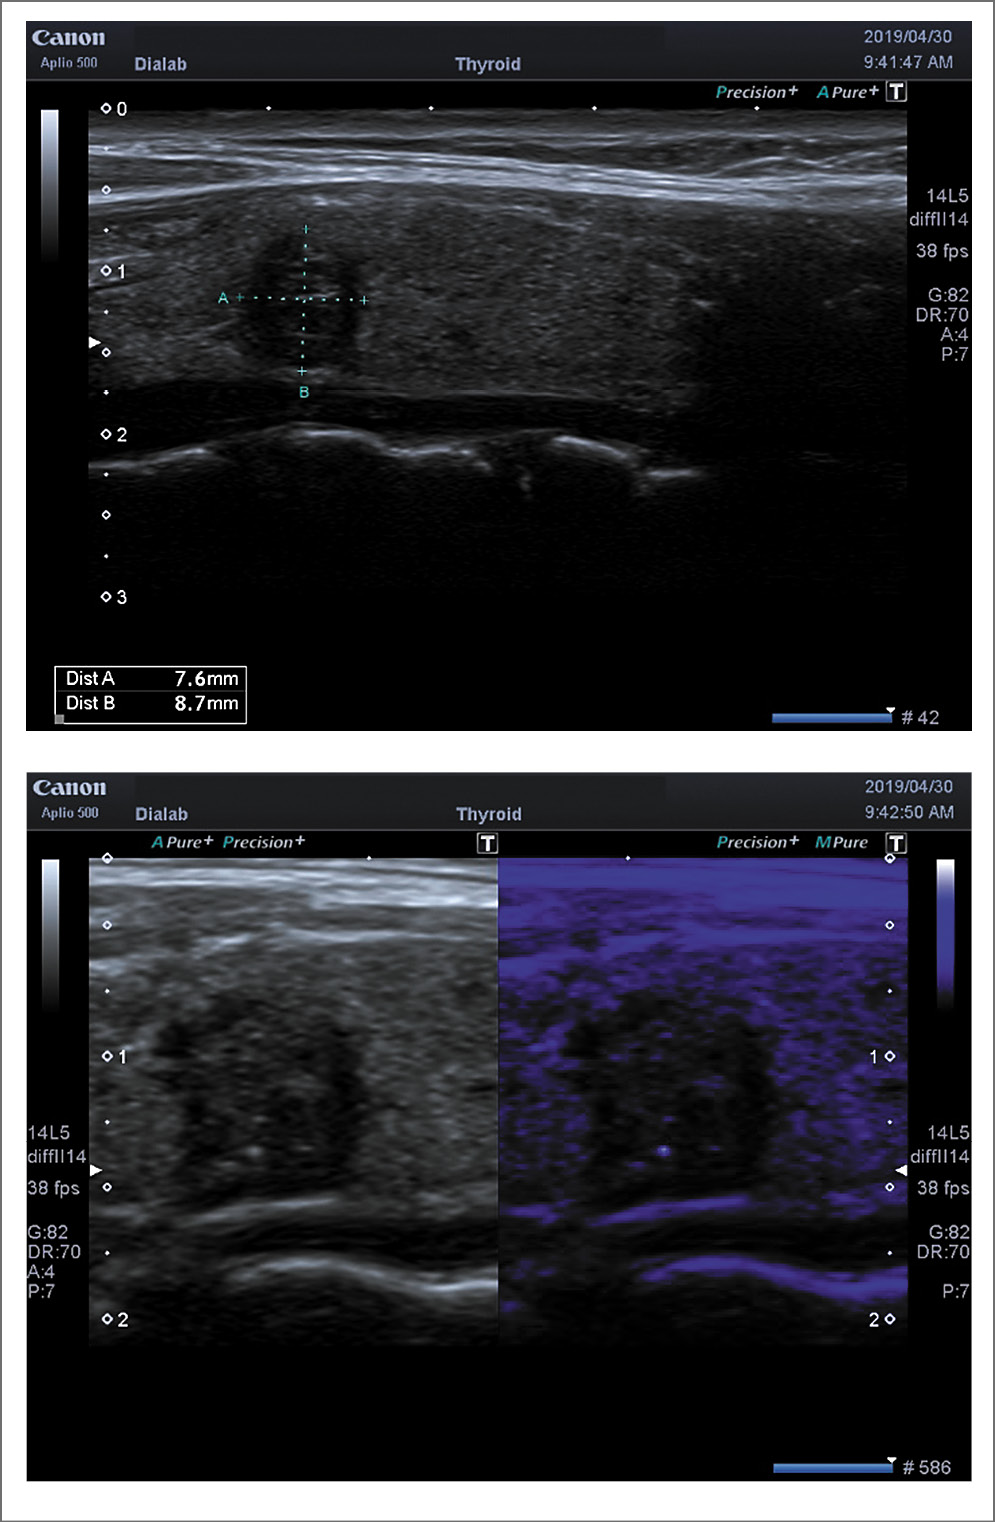

При определении риска злокачественности узлов ЩЖ по системе TI-RADS получены следующие данные: при ПР к категории 3 отнесены 13 (17,3%), 4а – 21 (28%), 4б – 31 (41,3%), 5 – 10 (13,4%) пациентов (рис. 1). При ПР на фоне АИТ в категорию 3 вошли 3 (15%), 4а – 7 (35%), 4б – 8 (40%), 5 – 2 (10%) больных (рис. 2).

Рис. 1. ПР, TI-RADS 4B (2D-режим). Небольшой узел с микрокальцификатами и преобладанием вертикального размера

Рис. 2. ПР на фоне АИТ, TI-RADS 4B (2D-режим). Изоэхогенный узел с неровными нечеткими контурами, микрокальцификатами, с единичным перинодулярным кровотоком.

При определении качественных критериев по системе Tsukuba–Ueno большинство больных ПР отнесены к 3-му типу – 49 (65,3%): 3а – 10 (13,3%); 3б – 39 (52%). Тип 4 определен у 24 (32%), тип 5 – у 2 (2,7%) больных (рис. 3). В группе больных ПР на фоне АИТ преобладающее большинство отнесены к 3б типу – 14 (70%), 5 (25%) – к 4-му типу и 1 больной – ко 2-му типу (рис. 4).